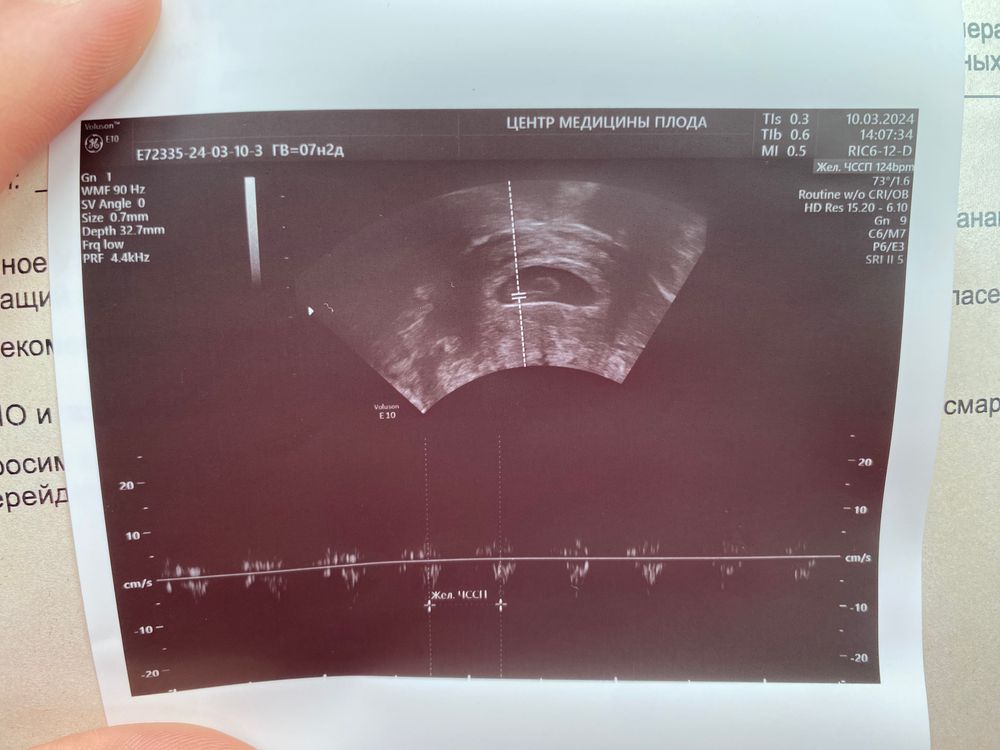

УЗИ 6 нед 3 дн

Мне кажется или написано на снимке 7 нед 3 дня?

Екатерина, не кажется)) овуляция была на 21 день цикла, поэтому реальный срок на неделю меньше

Екатерина, 19 января последние месячные, овуляция 8 февраля) а вы не знаете когда была овуляция?)

ЗдОрово)У вас 6 акушерских недель или эмбриональных?

Галя, акушерский срок)